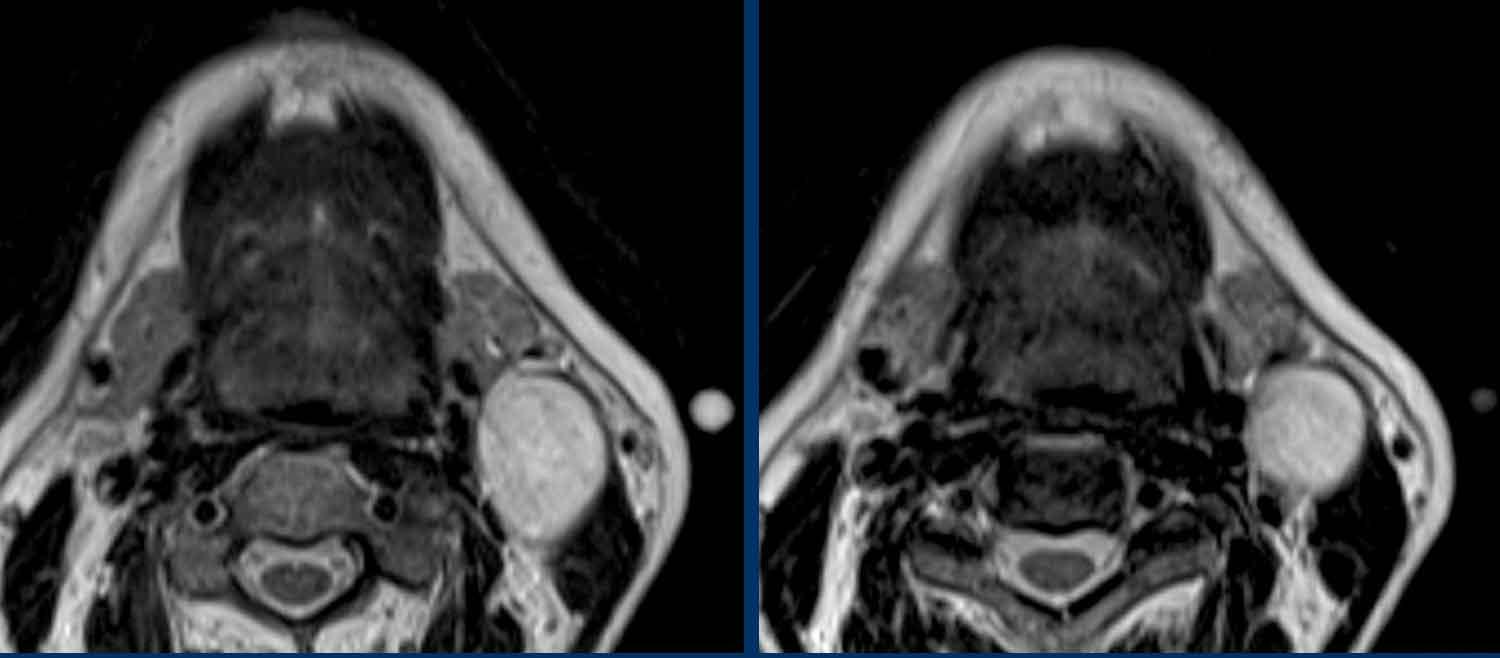

Ung thư hầu họng liên quan đến HPV

Các hình ảnh này thuộc về một nam bệnh nhân 69 tuổi với khối sưng vùng cổ trái.

Tổn thương được báo cáo là nang khe mang.

Mức dịch-dịch (đầu mũi tên) được cho là mảnh vụn do nhiễm trùng hoặc chảy máu trước đó.

Trong quá trình theo dõi, khối sưng tăng kích thước và mười tháng sau tổn thương được phẫu thuật cắt bỏ.

Kết quả giải phẫu bệnh: Di căn của ung thư biểu mô tế bào vảy, dương tính với dấu ấn P16.

Đây là dấu ấn chỉ điểm tình trạng dương tính với virus u nhú ở người (HPV).

Trong quá trình tìm kiếm khối u nguyên phát, bác sĩ chuyên khoa Tai Mũi Họng phát hiện amidan bên trái có kích thước hơi lớn hơn.

Lưu ý rằng vùng giảm tín hiệu trên bản đồ ADC nhỏ hơn vùng tăng tín hiệu trên DWI (b1000).

Điều này có nghĩa là chỉ có phần trung tâm của amidan là ung thư. Khối ung thư nằm sâu trong các hốc của amidan và thường không nhìn thấy được khi nội soi.

Sinh thiết xác nhận ung thư biểu mô tế bào vảy liên quan đến HPV và bệnh nhân được điều trị bằng xạ trị.